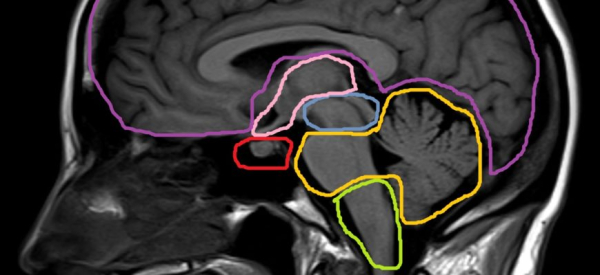

1. Магнитно-резонансная томография (МРТ)

МРТ – это метод исследования, основанный на использовании магнитных полей и радиоволн. Этот метод позволяет с высокой точностью визуализировать и оценить состояние цистерн головного мозга. При МРТ проводится серия снимков, которые позволяют врачам видеть структуру, размеры и форму цистерн. МРТ-исследование позволяет обнаружить наличие различных патологий, таких как опухоли, кисты и воспаление. В случае необходимости, в ходе МРТ можно также провести дополнительные функциональные исследования для оценки работы головного мозга.